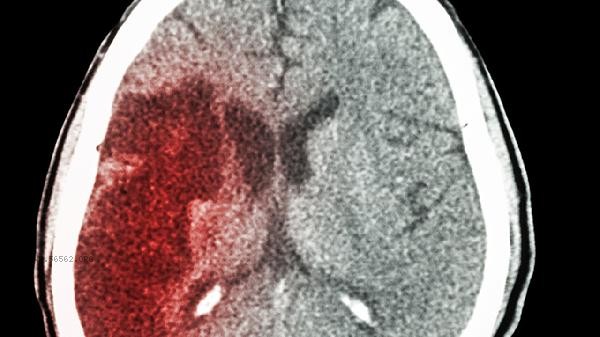

Daily care for anxiety after cerebral infarction requires maintaining a regular schedule, ensuring 7-8 hours of sleep every day, and taking a nap of no more than 30 minutes. Choose foods rich in tryptophan, such as millet and bananas, and limit caffeine intake. Perform soothing exercises such as Baduanjin at least 3 times a week to avoid blood pressure fluctuations caused by intense activity. It is recommended that family members accompany and participate in community rehabilitation activities to gradually rebuild their social circle. Regularly review head CT scans to assess brain recovery. If there is persistent emotional loss, timely follow-up visits should be made to adjust treatment plans.